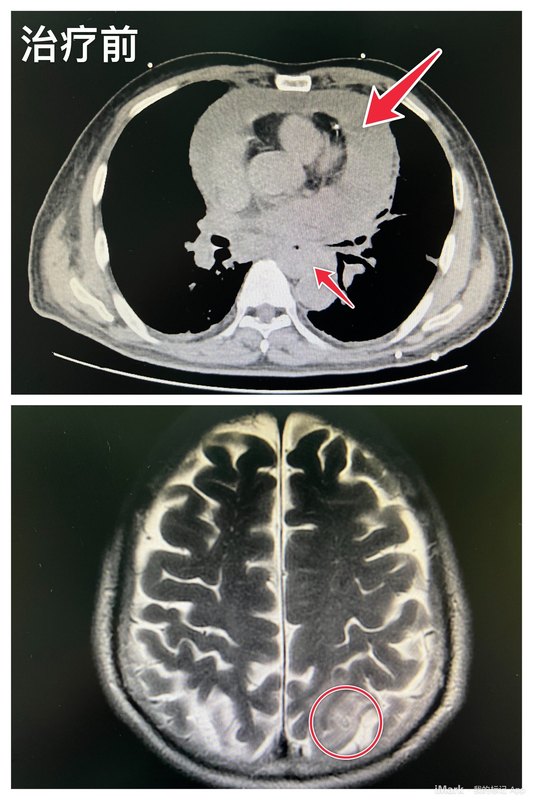

晚期食管鳞癌合并急性化脓性心包炎综合治疗显奇效

患者四个月前在外院诊断为食管鳞癌,转入我科的时候情况非常糟糕,严重的进食障碍,双侧胸腔、心包大量积液,心衰,发热,电解质紊乱。我们首先果断行左胸腔探查,发现患者心包积液是由于急性化脓性性心包炎所致!通过心包开窗引领、积极抗感染,患者心衰及发热得到控制缓解,这时又检查发现颅内有一处肿瘤转移灶。我们评估患者身体状况后予以化疗联合免疫新辅助治疗三个周期,患者吞咽困难症状有所缓解,颅内转移灶基本上消失,今日终于在胸腹腔镜下顺利完成食管肿瘤切除。回想整个处置过程可以说步步惊心,要是某个环节处理不及时,患者就可能危及生命。这里也要赞一下患者家属,自始至终支持配合医生,不抛弃不放弃,医患合力病人才能走到今天